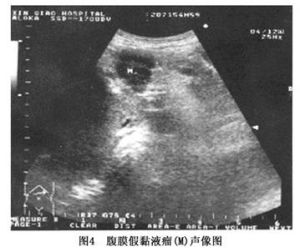

圖4其它輔助檢查:

(3)B超檢查:無創傷,費用低可靠,應作為首選。如果B超發現腹腔液性暗區略呈灰白色其內瀰漫分布粗大光點、光斑、光環緩緩晃動隨深呼吸體位變動加壓或衝擊探查見“禮花樣”飄動,應高度疑為腹膜假黏液瘤(圖3AB)。

表現為腹腔內壁或腸壁表面顯示不規則小囊狀無回聲區(如圖4所示);以及腹腔內大片的蜂窩狀無回聲區界線不清其內可見細小點狀回聲,隨著體位改變,可見細小點狀回聲在無回聲區內飄動。小囊腫一般無光滑而完整的囊壁,較多的小囊腫聚象在一起,則形成蜂窩狀結構。小囊狀結構亦可附著在肝臟、膀胱及子宮等器官的表面。根據聲像圖特徵,結合病史,此病的診斷並不困難